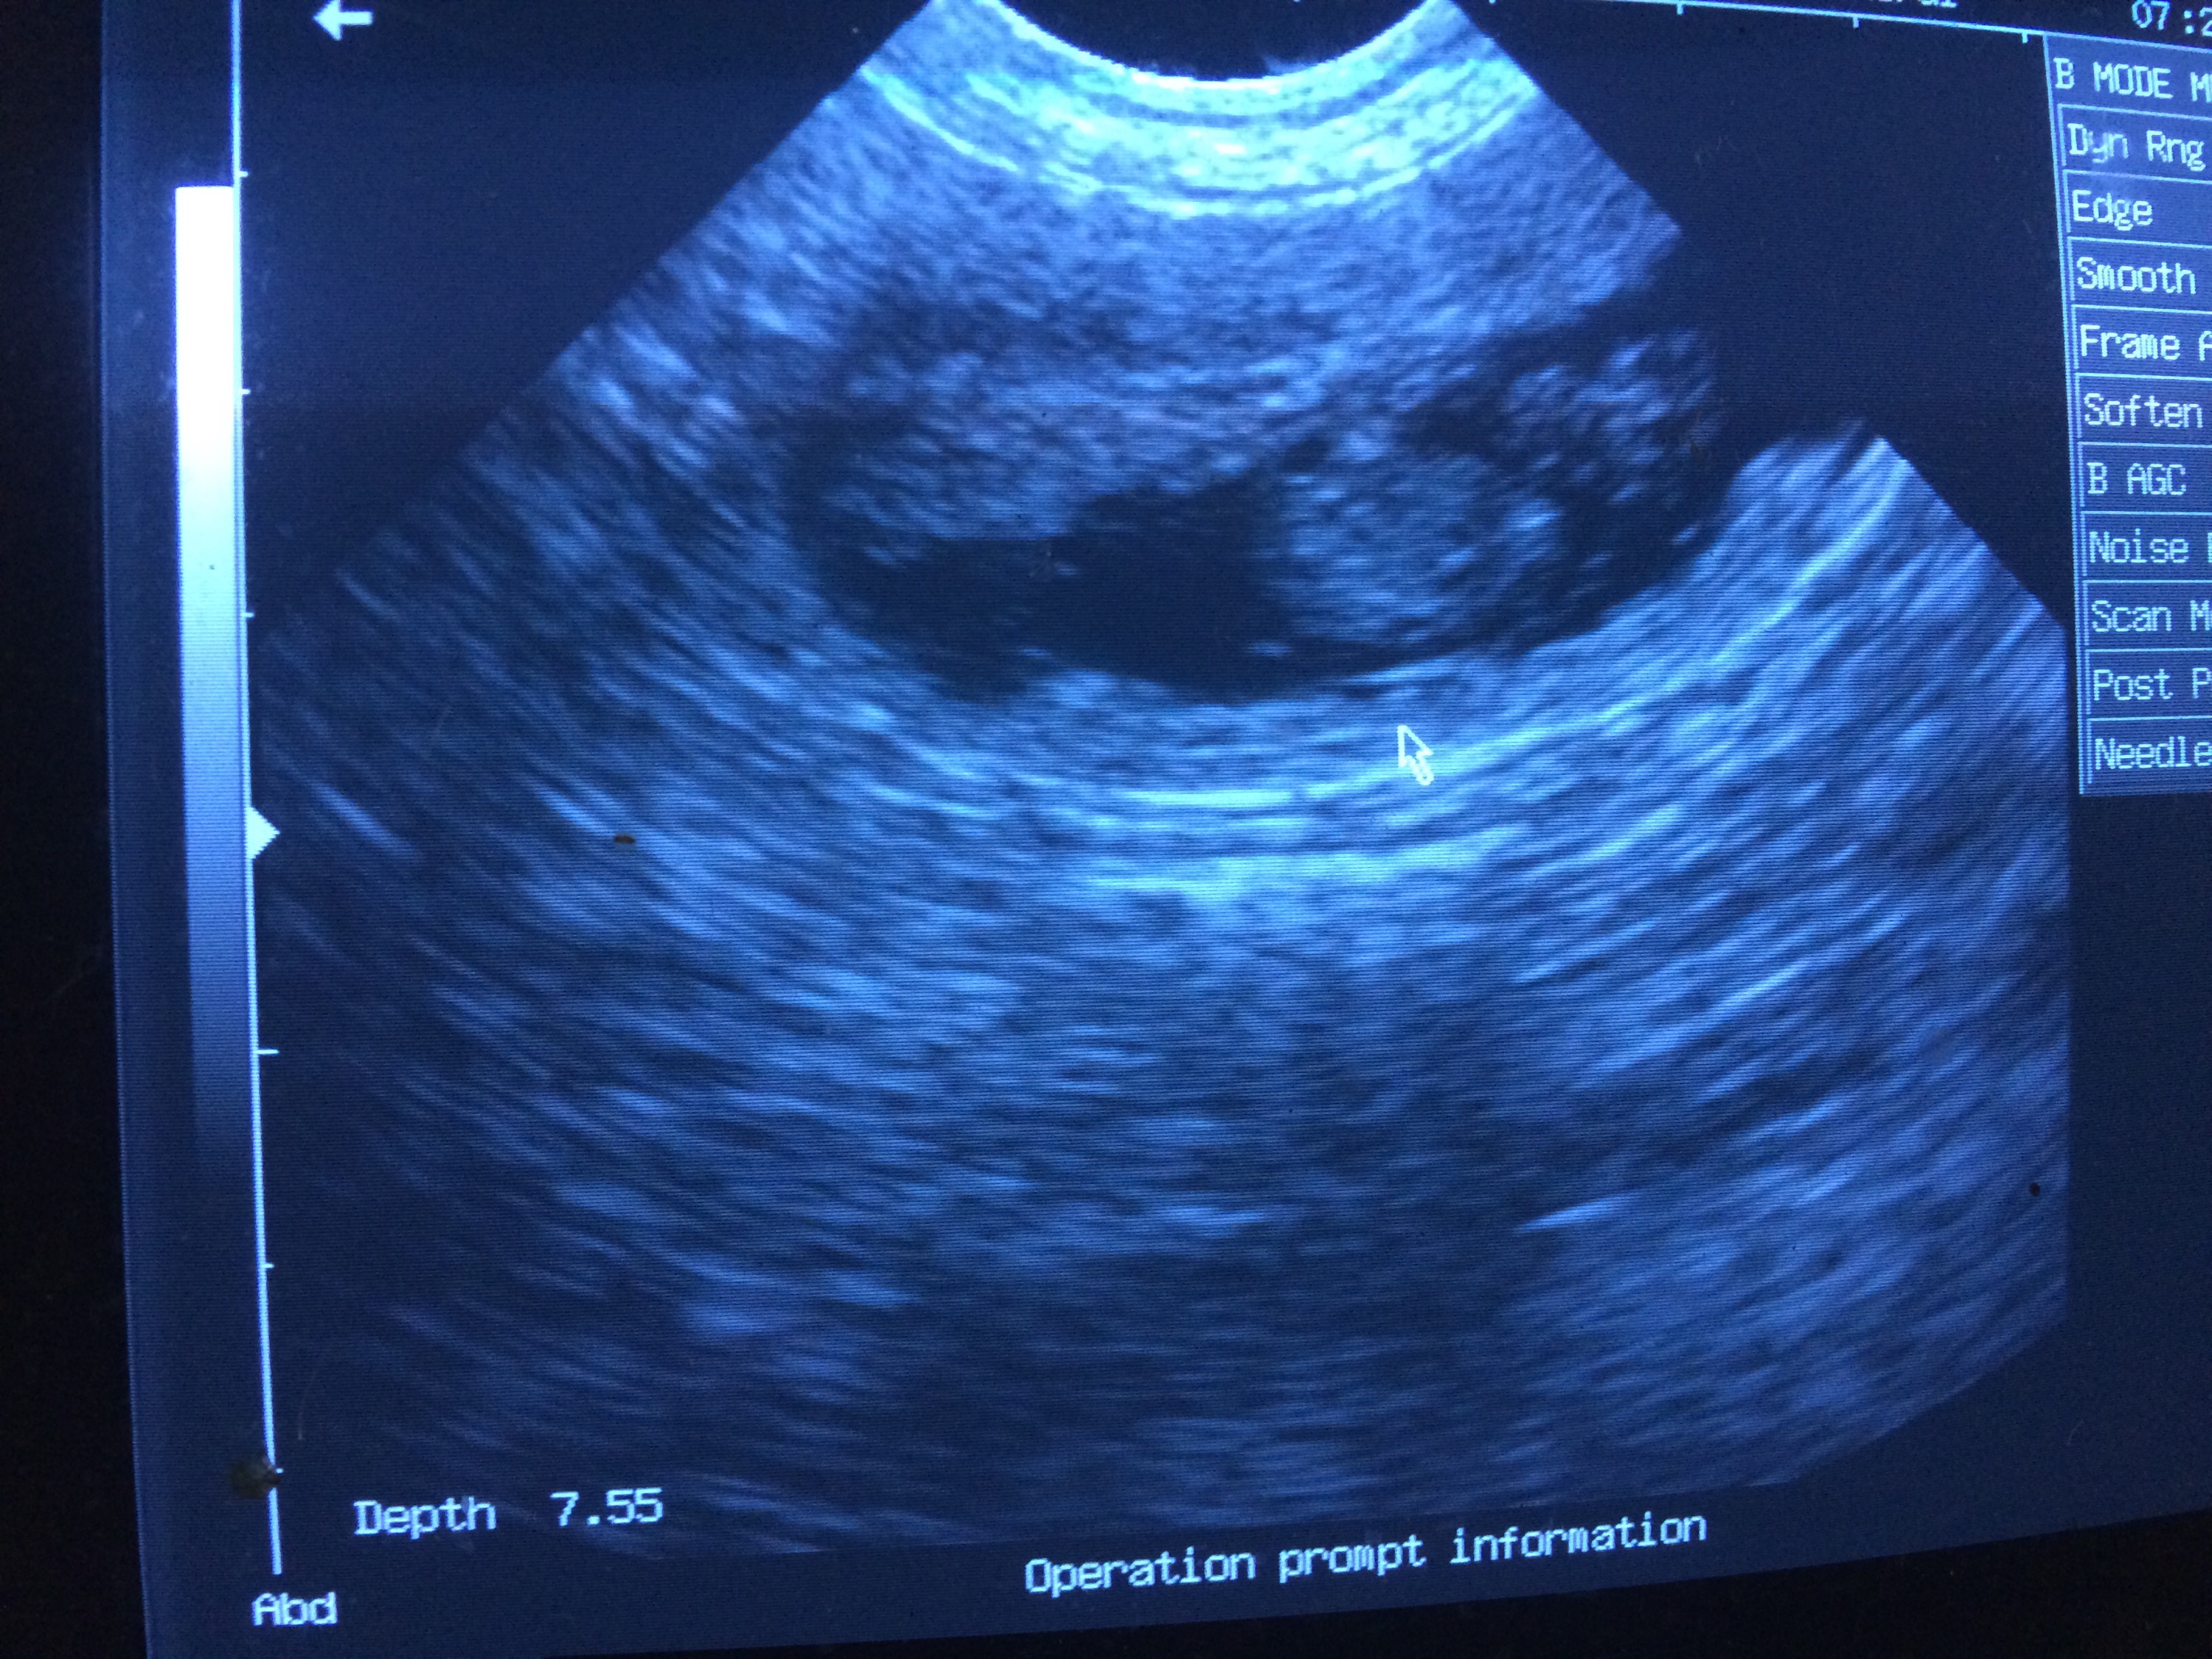

30 dagar har gått sedan parning och hon har gått upp 1 kg. Åkte in för att ultraljuda henne imorse för att se om där var några valpar. Men med de tecken jag har sett de senaste veckorna rådde det inga tvivel om att magen var full.

Vi fick se tre valpar på samma bild, det var en extremt häftig känsla. Fick även en bild på en valp med tassarna i luften.

Så nu är min magkänsla bekräftad. Valpar har hon. Sen hur många, det återstår att se. Med tanke på att de låg tätt så är där nog några stycken.